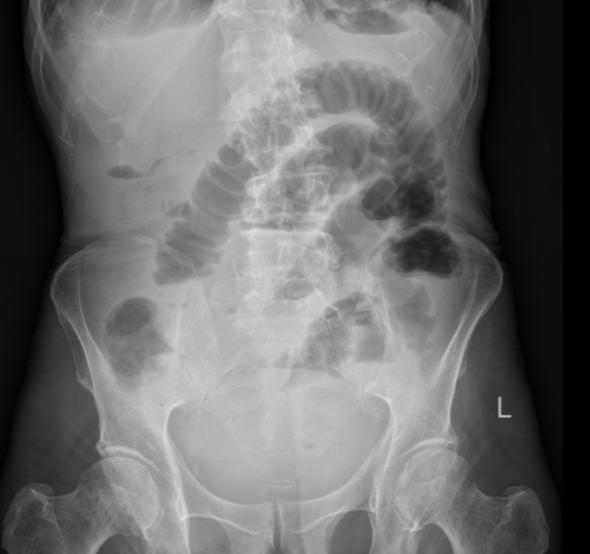

王大爷因腹痛、腹胀一周,伴呕吐、停止排气排便四天,被紧急送入我院肿瘤外科二病区。经影像学检查,王大爷被明确诊断为低位小肠梗阻。这意味着梗阻发生在小肠末端,肠道内容物完全无法下行,大量消化液和气体在肠腔内积聚,肠壁被持续撑胀,随时可能缺血坏死、穿孔,引发致命性腹腔感染。

导管开始工作后,积聚的肠内容物被持续引出,腹胀腹痛的症状一天天缓解。老人的肠道功能慢慢恢复,复查腹平片显示梗阻情况明显好转。在护理团队的精心照料下,老人从卧床不起到能下地活动,从禁食禁水到逐渐恢复饮食,一天天好起来。2月24日,王大爷顺利出院,重新回归了正常生活。